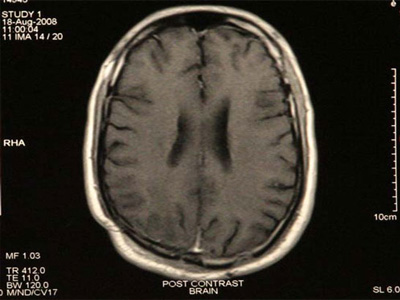

Dr. Sai Sudarsan is a well trained and an experienced Micro neurosurgeon and an Endo vascular neurosurgeon based in Star Hospital, Hyderabad.

He is a senior consultant in neurosurgery at Star Hospital, Hyderabad. He grew up at Tirupati, Andhra Pradesh and finished his basic medical schooling there. He did his masters in General Surgery at Kurnool, Andhra Pradesh and went to Sree Chitra Tirunal Institute of Medical Sciences, Trivandrum for his masters training in Neurosurgery. He has a very good experience in micro neurosurgery, neuroendoscopy, spinal instrumentation and stereotaxy. He also got trained in endovascular neurosurgery and is a part of an experienced endovascular team at Star Hospital, Hyderabad. He is known as the best spine doctor in Hyderabad.